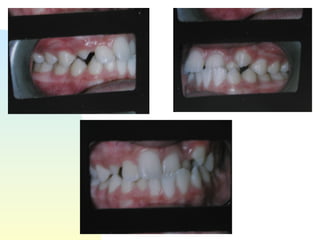

Patient   : J.R, male DOB :7/20/91, start of tx age: 12yr 9mo Ethnicity : American-born Hispanic, English-speaking Health Hx :  WNL, unremarkable Dental Hx :TMJ=WNL, OH=B+, midline=on, molar R&L= Cl 1, OB=40%, OJ= 1mm, dental anterior cross-bite, crowded max & mand anteriors, caries #15-O, #18-O,B, perio=WNL Psychosocial : Parents are separated,  1 younger sister,1 older sister.  Mom had ortho tx --- 4 premolars & 4-3rd molars extracted, “My braces hurt and I don’t want a lot of teeth pulled on my son”. Chief complaint :  “I don’t like the way my teeth stick out in front.”